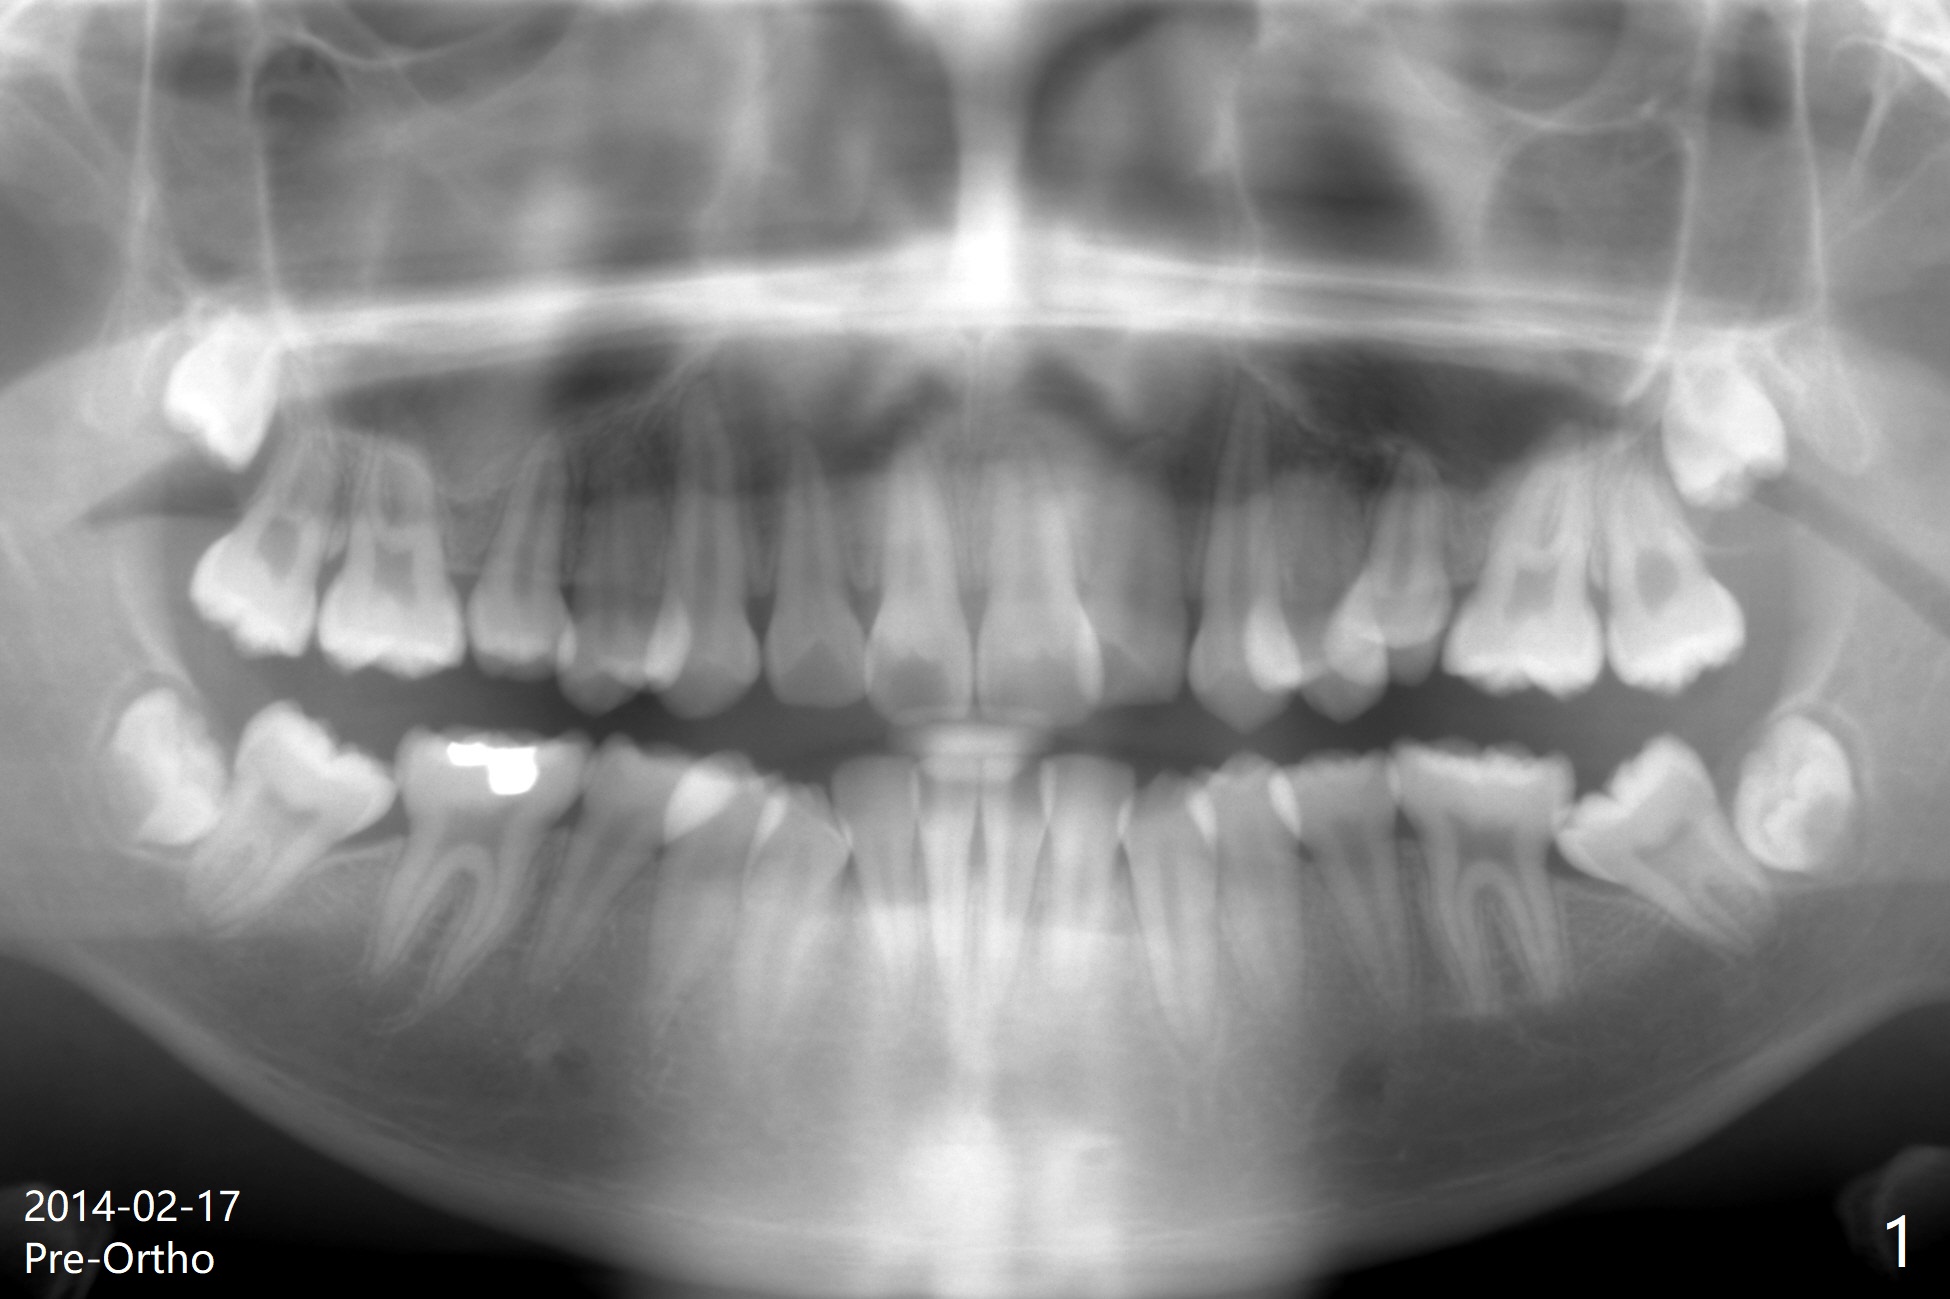

A 19-year-old man with history of orthodontic treatment (Fig.1,2) returns to office for #1,16,17,32 extraction with Collagen Plug placement at #17 and 32 (4-0 plain gut suture). The sockets heal in 4.5 months (Fig.3).